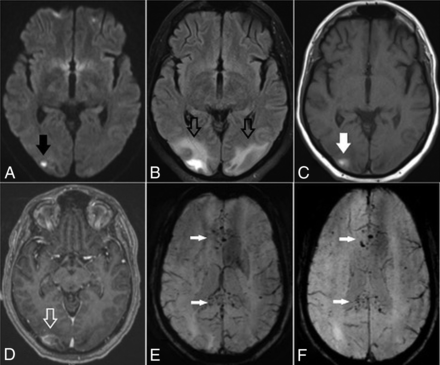

On March 25, she developed altered mental status, including lethargy and confusion, and was transferred to our hospital. In the emergency department, the patient was afebrile, with laboratory values notable for Cr = 1.65, blood urea nitrogen = 23, lactate = 2.3, and mild hyponatremia. Arterial blood gases were normal, and she denied cough, chest pain, and shortness of breath. The patient had variations in blood pressure, ranging from 115/72 to 178/83 mm Hg at admission. Chest CT demonstrated bilateral multifocal ground-glass opacities concerning for COVID-19 pneumonia due to its high prevalence in the region. Findings of a polymerase chain reaction test were positive for SARS-CoV-2 on March 27. Noncontrast head CT demonstrated edema in the bilateral parieto-occipital regions with associated mass effect and cortical sulcal effacement (Fig 3). MR imaging of the brain performed on March 27 revealed multiple areas of restricted diffusion with associated edema, most extensive in the posterior parieto-occipital lobes but also in the right frontal lobe, basal ganglia, and cerebellar hemispheres. The SWI sequence demonstrated extensive superimposed hemorrhages in the parieto-occipital region along with abnormal enhancement (Fig 4). Findings of concurrently performed MR angiography of the head and neck were unremarkable: Specifically, evaluation of the posterior circulation demonstrated a patent vertebrobasilar system. The patient remained afebrile with normal respiratory status, including oxygen saturation; after gradual improvement in her mental status, she was discharged.

Brain axial DWI (A), FLAIR (B), precontrast T1-weighted (C), postcontrast T1-weighted (D) and SWI (E and F) obtained after CT demonstrate bilateral posterior infarctions (white arrows, A), edema in the posterior parieto-occipital regions (white arrows, B), and some contrast enhancement (hollow white arrow, D; compare with C). Selected SWI shows extensive blooming artifacts compatible with hemorrhages predominantly in the cortex (white arrows, E and F). Findings are more pronounced on the right side.